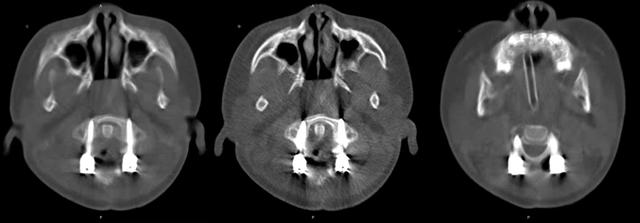

al-align:top;”> 孩子,望你早日康复! 这是一个关于 2岁宝贝的故事 为何这个幼儿平地摔倒,外表毫无受伤痕迹,却出现全身瘫痪,甚至呼吸功能衰竭? …… 为何凌晨时分,重医一院急诊科传来了救护车急促的汽笛声? …… 病史 患儿女,2岁零11个月; 于家中玩耍时平地跌倒致短暂意识丧失,苏醒后四肢瘫痪,自主呼吸微弱,病情危急! 为什么? 影像 患儿在当地医院作了急诊CT检查,发现…… CT显示:寰枢关节不稳 MRI:患儿呼吸不好,病情已不允许作了 分析 1. 尽管没有MRI检查,但根据CT显示的寰枢椎不稳,结合患儿四肢瘫痪,自主呼吸微弱的症状,颈延髓损伤明确; 2. 临床诊断:1)寰枢椎脱位 2)颈延髓损伤 怎么办? 方案 刻不容缓,做急诊手术准备! 寰枢关节不稳必须立即解决,否则有延髓再损伤的风险! 急诊手术:“寰枢椎复位+颈1-2融合内固定术+后路寰枕减压” 难点 患儿年龄小且发育较差,身高较同龄幼儿少10cm,体重仅仅11kg,上颈椎手术本就属脊柱高危手术之一,而幼儿的上颈椎骨质细小,在幼儿的上颈椎进行内固定手术,更是难上加难; 经验 重庆医科大学附属第一医院虽然是一所主要面向成人的综合性医院,但本院神经外科脊柱亚专业组,在幼儿脊柱手术方面具有丰富经验,尤其是对幼儿上颈椎损伤、颅底凹陷、先天性颅颈畸形、寰枢椎脱位等疾病,手术技术娴熟,成功完成过从2岁至13岁不同年龄幼儿的上颈椎手术。 既往病例文章分享: # 从13岁到2岁 # 一例“复杂”幼儿颅颈畸形 # 挑战幼儿 —— 3岁11月颅颈畸形手术病例分享 # 病例分享 || 幼儿复杂颅颈畸形 ……………… 本例患儿的手术在入院后2小时立即进行,并成功完成。解决了患儿寰枢椎不稳的风险,为其后续治疗的安全性提供了强有力的保障。 术后情况 术后CT示寰枢椎完美复位,寰枕区减压充分, 避免了患儿颈延髓神经功能二次损伤可能,为康复争取时间! 小宝贝术后虽然颈椎稳定了, 也减压了。 但是一时还无法脱离呼吸机, 也无法离开监护室, 无法见到自己爸爸妈妈! 不要害怕,宝贝! 重医一院神经外科脊柱亚专业组 和神经重症亚专业组的叔叔阿姨们 以及神经外科的护士小姐姐们, 会一直守护在你身边, 为你保驾护航! 宝贝加油! 相信你一定能战胜病魔,茁壮成长! 老晏说 幼儿脊柱疾病,亦在重庆医科大学附一院神经外科!